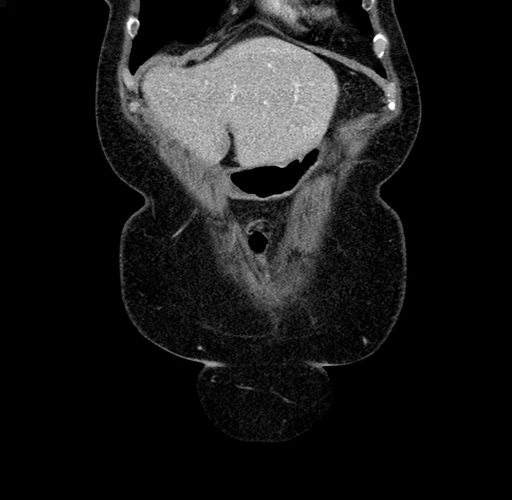

Pre-Chemo: Coronal Venous